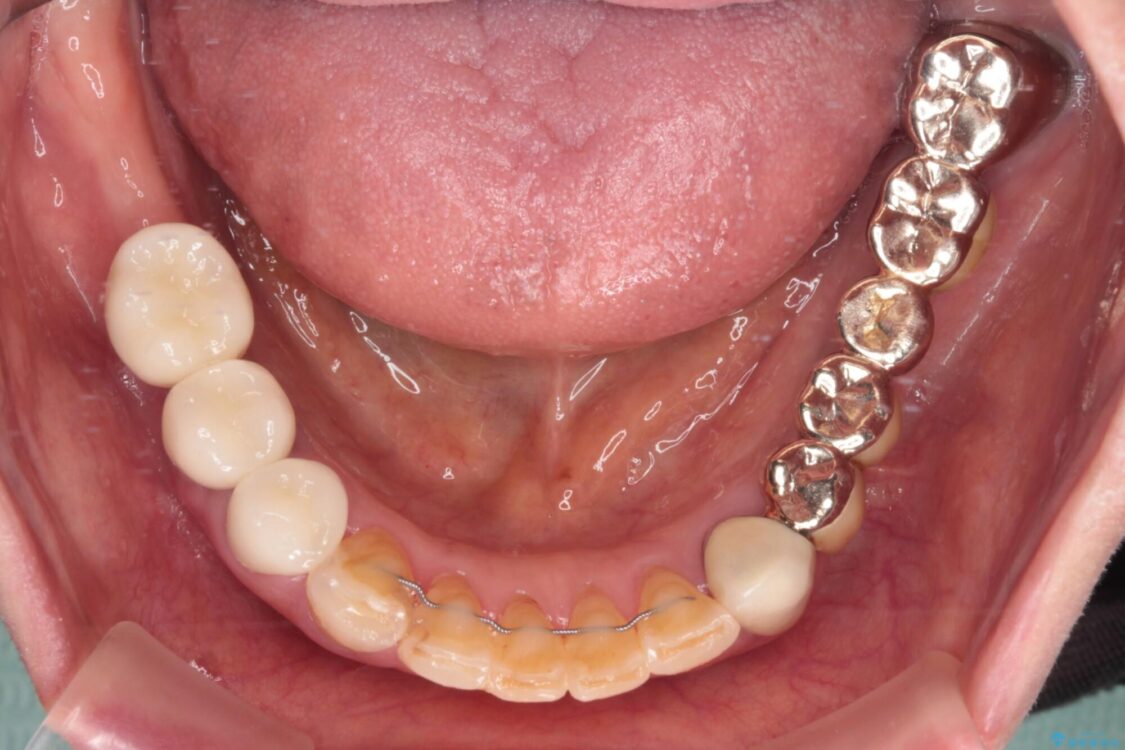

処置を予定していた歯を仮歯に変えた時点で、下顎前歯の部分矯正を行うかどうかを尋ねたところ、折角なので行いたいと言うことでしたので、矯正治療を行うこととしました。

インプラント埋入や根管治療治療など、治癒に一定の期間を要する処置の合間に矯正治療を行うことで、効率的に治療を進めて行くことができました。

治療後